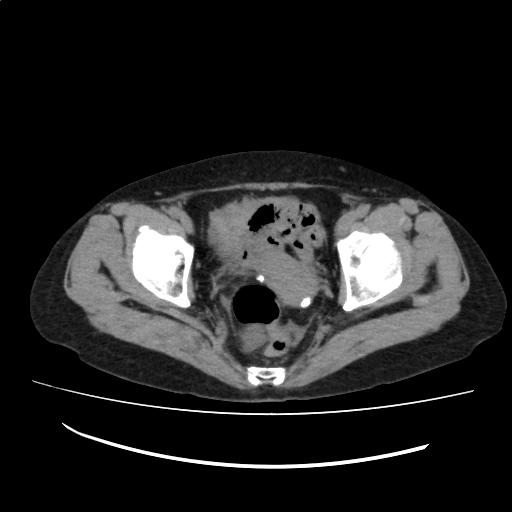

結腸憩室を認める。

石灰化を伴う子宮筋腫を認める。

大動脈周囲にリンパ節の病的腫大を認めない。

腹水を認めない。

(Impression)

前回検査と比較して著変はない。

CT画像136

(134/198)